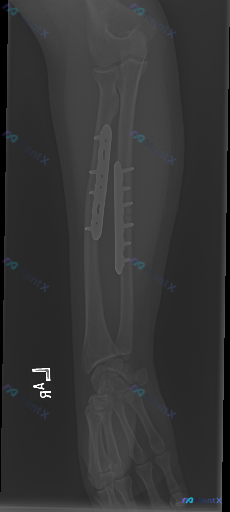

整理到一张左前臂正位X光片的读片资料: 基本背景:左前臂尺桡骨骨折术后复查 影像观察到的基础信息: - 尺、桡骨干均有金属接骨板+多枚螺钉固定 - 骨折断端对位对线尚可,未见明确内固定松动、断裂或移位 - 骨折区域可见初步骨痂生长影 - 腕关节、可见的部分肘关节结构尚完整,关节间隙无明显狭窄/增宽...